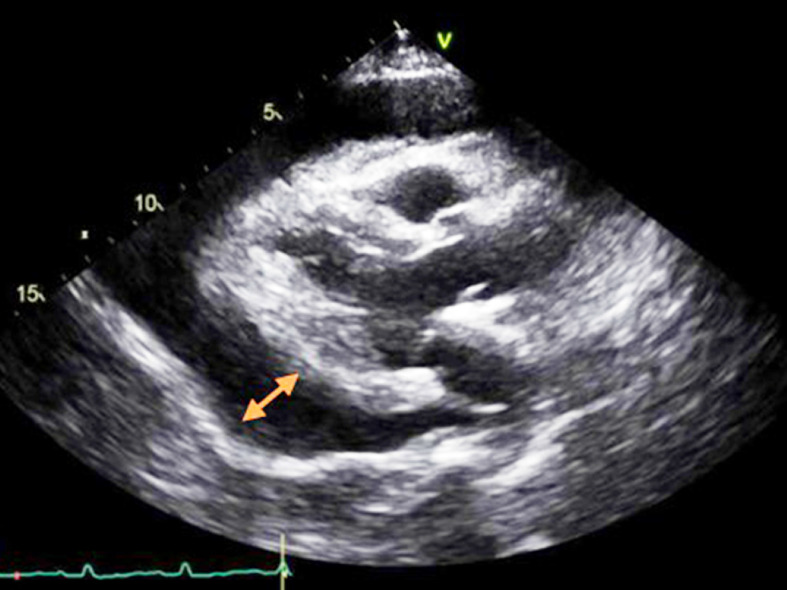

Case summary: We report the case of a 22-year-old immunocompetent female who presented to the emergency department with acute shortness of breath, fatigue, and dizziness due to symptoms suggestive of an influenza-like illness. Laboratory and imaging findings revealed a large circumferential pericardial effusion suggestive of cardiac tamponade. Subsequent investigations confirmed influenza B infection. The patient was managed with pericardiocentesis, oseltamivir, nonsteroidal anti-inflammatory drugs, colchicine, and supportive care, resulting in complete recovery. This case highlights the significance of considering influenza as a potential cause of acute cardiac complications and the importance of early diagnostic and therapeutic interventions to prevent morbidity and mortality.